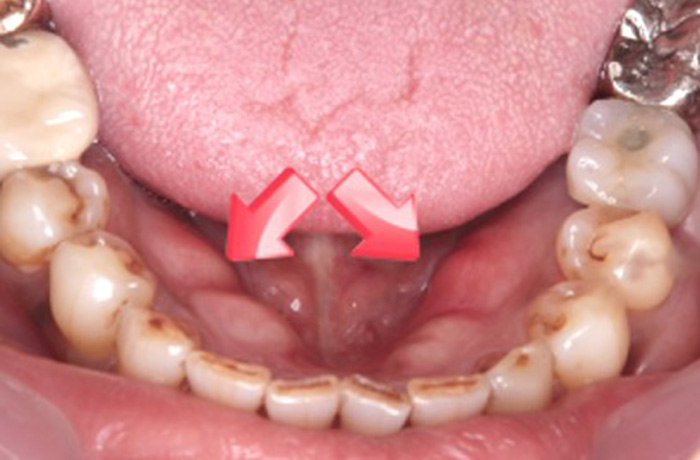

2 ベロを見ると凸凹している

朝起きて歯を磨く前に鏡で自分の舌の形を確認してみてください。もし、写真のように舌が凸凹している場合は、確実に食いしばりをしています。

また、夜間だけでなく昼間のスマホいじりなどで、舌を歯に押し当てることで陰圧形成を行い食いしばることで、ベロが写真のように凸凹になる方が非常に増えています。

私は、これを「スマホ舌」と呼んでいます。